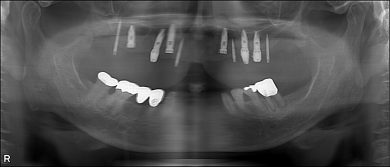

当日のレントゲンを見た瞬間、その記憶は鮮明に蘇りました。

18年前に私がインプラント治療を担当させていただいた患者さんだったのです。

その方は現在90歳。長い年月を経て再び当院に来院してくださいました。

術後18年 下顎臼歯は当初から使えるまで使ってインプラントにしようと話してましたが、今もなんでも咬めるということですので、90歳の今このまま使っていただいています。今後次の治療になる時は、訪問診療ですね。

18年後の補綴。クラシカルですが、十分機能しています。

歯科医師ならではの“あるある”ですが、名前では思い出せなくても、レントゲンを見れば当時の治療の記憶が一瞬で蘇ることがあります。

今回もまさにそうでした。

18年前に埋入したインプラントの形、位置、周囲の骨の状態を見た瞬間に、当時のオペ室の空気感まで思い出したのです。